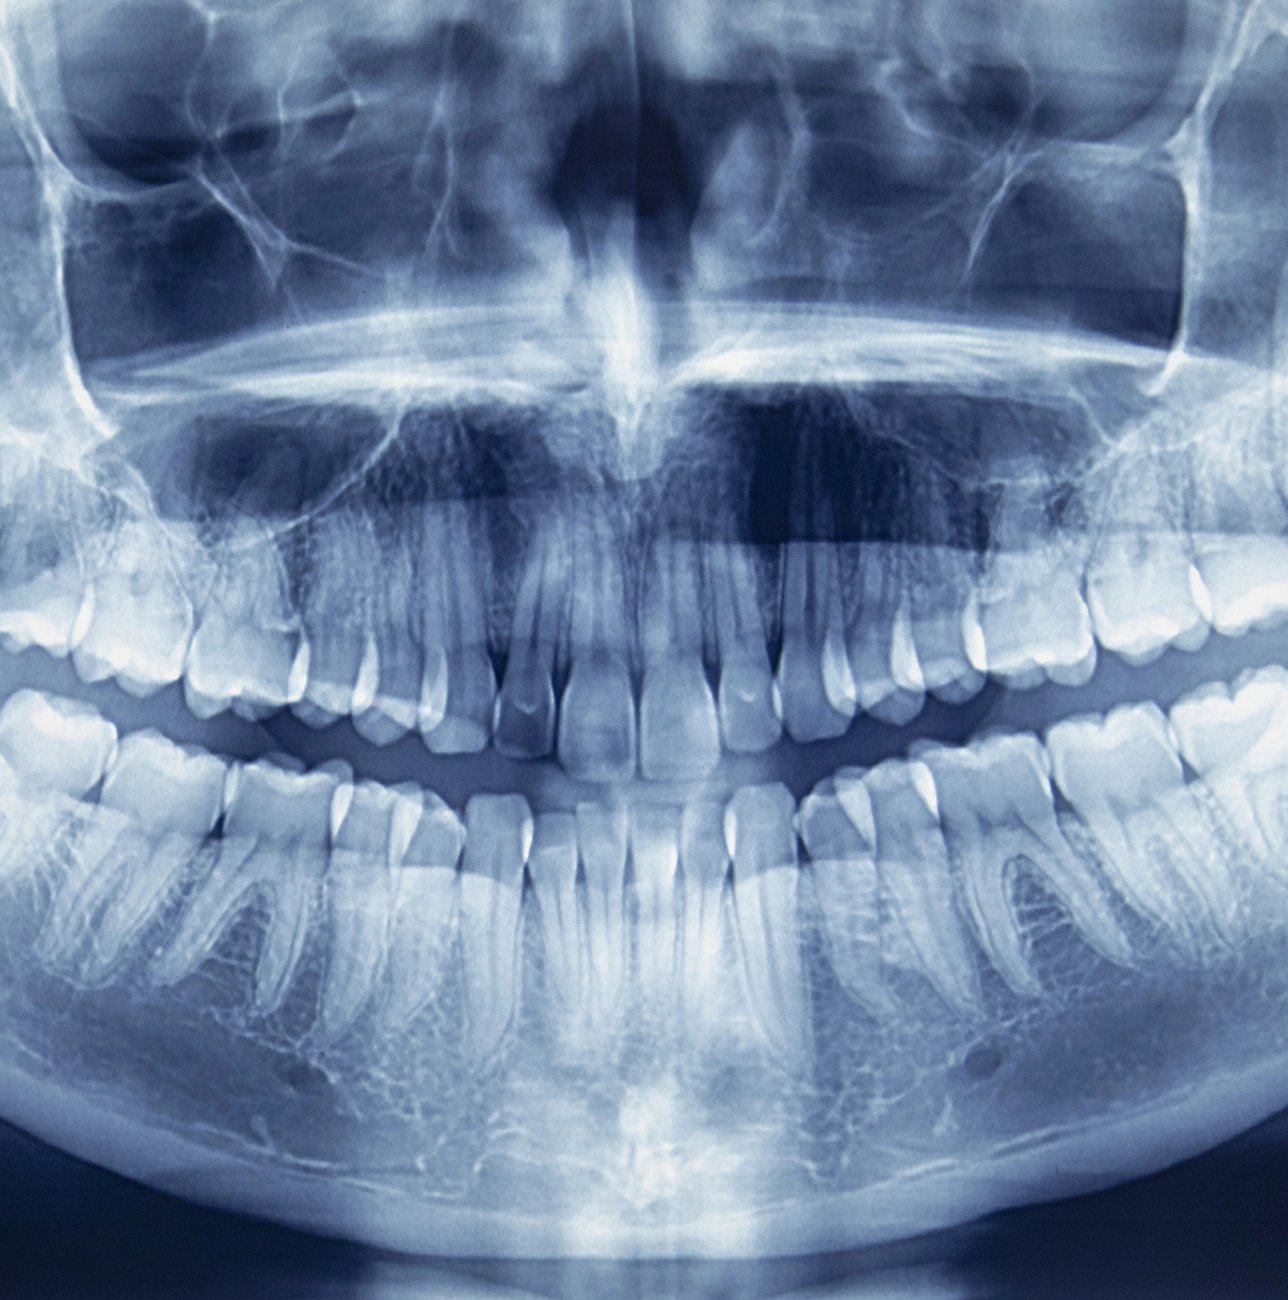

Schäden frühzeitig erkennen durch Röntgen.

Röntgenbild

Unverzichtbar für die Diagnose

Röntgenaufnahmen helfen, vorhandene Schäden rechtzeitig zu entdecken. Die Zahnröntgenaufnahme ist deshalb ein unverzichtbares Mittel zur Diagnose-Erstellung und zur Planung einer Behandlung.

Viele Zahn- und Gewebeschäden im Mund beginnen im Verborgenen. Besonders die Zahnzwischenräume und jene Bereiche der Zähne und des Knochens, die vom Zahnfleisch bedeckt sind, können von blossem Auge nur ungenügend beurteilt werden. Röntgenaufnahmen helfen, vorhandene Schäden rechtzeitig zu entdecken. Die Zahnröntgenaufnahme ist deshalb ein unverzichtbares Mittel zur Diagnose-Erstellung und zur Planung einer Behandlung. Sie stellt zudem ein wichtiges zahnmedizinisches Dokument dar.

Vom einfachen Einzelzahnröntgenbild bis zu computerunterstützten dreidimensionalen Schichtaufnahmen der Zähne und des Kiefers gibt es eine Vielzahl unterschiedlicher Aufnahmetechniken.